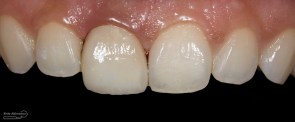

Foto klinis setelah pemasangan crown

“waah…. bagus doook…” ucap pasien pas diberikan kaca untuk melihat hasilnya

Alhamdulillah ekspektasi pasien terpenuhi dan ini yang tidak bisa dinilai dengan apapun, kita sebagai operator rasanya tuh bahagia banget… iya gak sih? apa gue yang lebay ya hahaha 😀